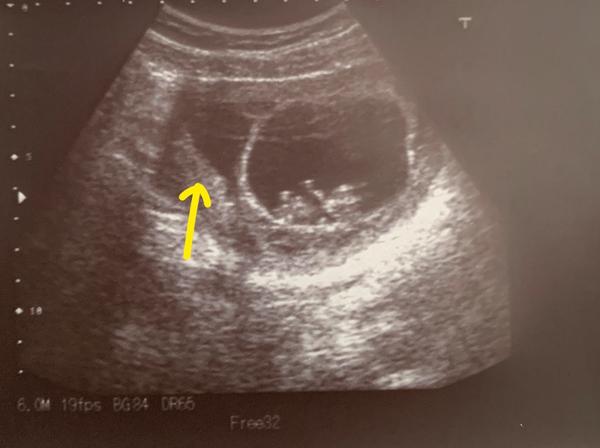

Potřebuji asi poradit nebo uklidnit. Jsem po mimoděložním únorovém těhotenství a momentálně i po IVF, které se zdařilo na první dobrou.🙏 Jsem teď v 10tt. Vše je skvělé, nezvracím, nemám velké obtíže, miminko na ultrazvuku mává, přetáčí se a je to moc hezký. Jenže mi doktor řekl, že tam mám i hematom, se kterým nejde nic dělat a musím vydržet než se vstřebá nebo až bude mimčo tak veliké, aby to pro něj nebylo nebezpečné. Ale že může i prasknout, z čehož mám strach. Nicméně vím, jak se mám chovat, byla jsem poučena a kvůli IVF beru i progesoteronové čípky. Prý se ale jinak mohu chovat úplně normálně, nijak zvlášť neležet. Jen netahat těžké věci. To vše dělám, ale i během dne polehávám kvůli lepšímu pocitu. Chtěla jsem se prosím zeptat na vaše zkušenosti s hematomem, se kterým jste dlouho nekrvácely, jestli mám očekávat prasknutí nebo se vám vstřebal? Dávám sem utz fotografii mého hematomu -> vede k němu šipka. Ještě mě zajímá jestli patří k těm velkým? Moc bych si přála abych si mohla užívat už těhotenství beze strachu. Moc děkuji za rady a zkušenosti.